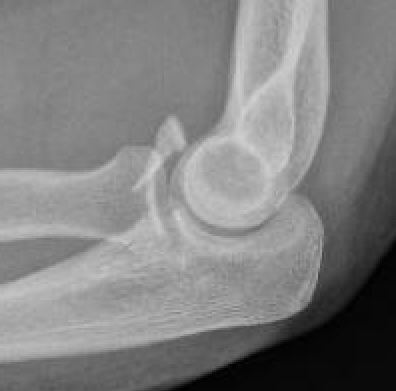

Regan and Morrey classification of transverse coronoid fractures

Elbow stability related to size of coronoid fragment

Coronoid Process Classification

Type I Type II Type II

Small coronoid process fracture 50% of coronoid process > 50% coronoid process

Usually stable

Capsular attachment

Elbow unstable

Capsule + MCL attachment

Coronoid Fracture Type 1 coronoid Type 3 Coronoid Fracture